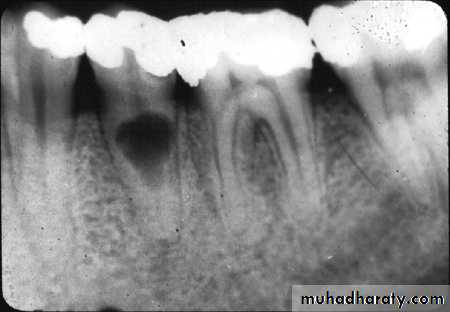

• Clinically:“Pink Tooth” appearance• Radiographic changes:

– Radiolucent enlargement of pulp canal

– Original root canal outline distorted

– Bone changes are seen only when root perforation into periodontal ligament takes place.

• Pulp tests: Positive, though coronal portion of pulp is necrotic, apical pulp could be vital